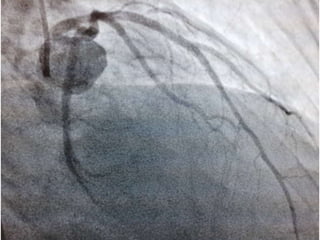

CASO CLINICO # 3

MASCULINO 65 AÑOS DE EDAD

DIABETES TIPO 2 DESDE HACE 15 AÑOS POBRE CONTROL METABOLICO

DISLIPIDEMIA. OBESIDAD GRADO II.

CUADRO CLINICO: ANGINA DE PECHO ATIPICA. CHEQUEO DE RUTINA. ECG DE

REPOSO NORMAL. PRUEBA DE ESFUERZO POSITIVA Y PRECOZ PARA ISQUEMIA.

TA 120/ 68 mm Hg. FC 67/min Fr 13/ min

Glucosa en Ayunas 215 mg /dL. Colesterol total 260 mg/dL, LDL 135 mg d/L

Creatinina 1.2 mg/dL

EXAMEN FISICO ANODINO

CASO CLINICO #3 MASCULINO 65 AÑOS DE EDAD DIABETES TIPO 2 DESDE HACE 15 AÑOS POBRE CONTROL METABOLICO DISLIPIDEMIA. OBESIDAD GRADO II. CUADRO CLINICO: ANGINA DE PECHO ATIPICA. CHEQUEO DE RUTINA. ECG DE REPOSO NORMAL. PRUEBA DE ESFUERZO POSITIVA Y PRECOZ PARA ISQUEMIA. TA 120/ 68 mm Hg. FC 67/min Fr 13/ min Glucosa en Ayunas 215 mg /dL. Colesterol total 260 mg/dL, LDL 135 mg d/L Creatinina 1.2 mg/dL EXAMEN FISICO ANODINO